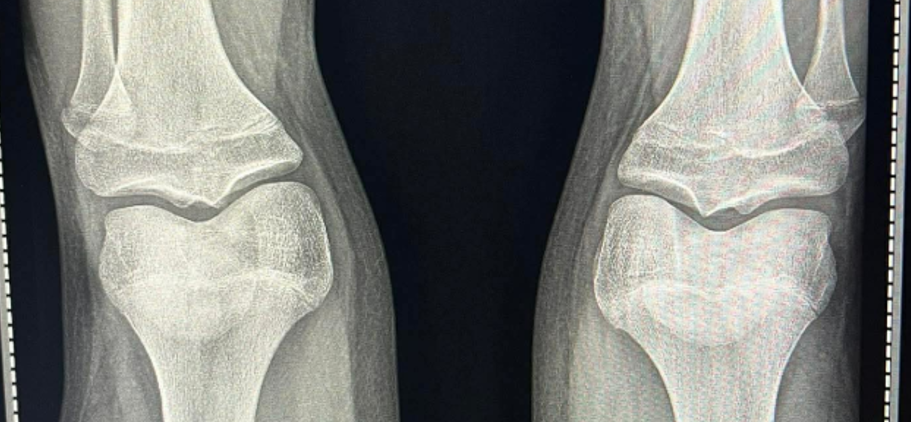

my jew doctor said its too late to take it now shouldve came last year context im 15.9 months and bone age is 15 and e2:near 51 and this is my growth plates

Growth plates looks closed/almost closed.